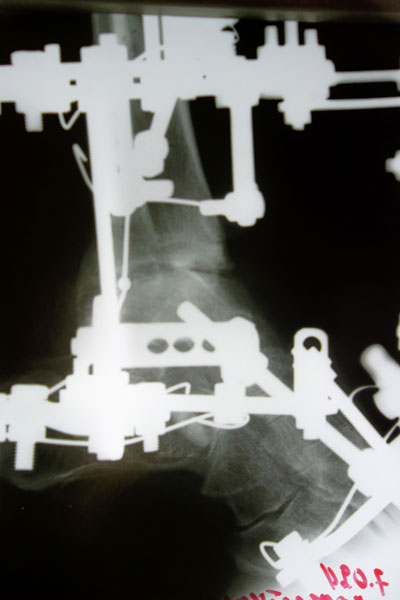

Рентген через 1,5 месяца после операцииХожу на костылях, перевязки за 150 км приезжаю делать в клинику один раз в 10 дней. Там же мне и делают компрессию по всем стержням. :)